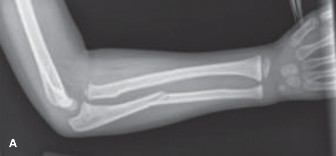

CASE 5 A 4-year-old girl fell from a playground structure, suffering the injur…

CASE 2 A 6-year-old boy fell from the monkey bars a few hours ago and had imme…